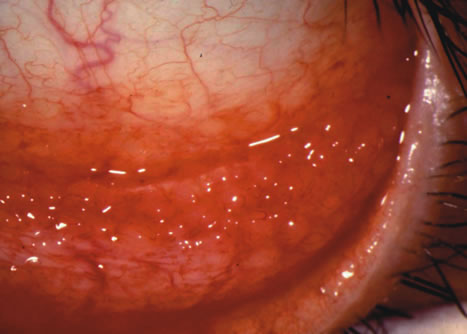

Clinically, follicles are yellowish to grayish white, discrete, round elevations of the conjunctiva. The central part of the follicle is avascular, but dilated blood vessels may surround the base and sweep up from the base over the convexity (Figs. 1 and 2). Follicles are 0.2 to 2 mm in size, although larger follicles may be seen, particularly in chlamydial disease.3

Fig. 2. Follicular conjunctival reaction in the inferior fornix.